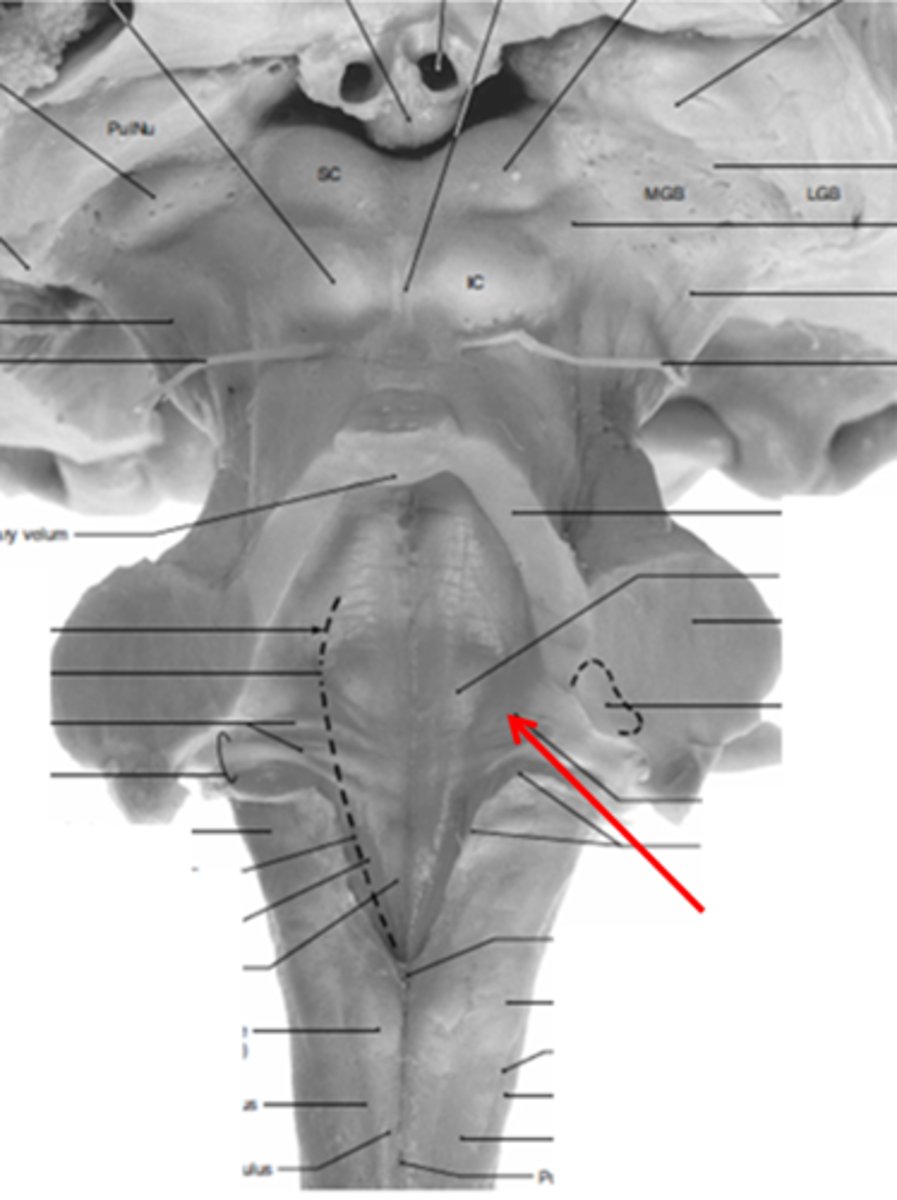

two ridges of tissue on the ventral aspect of the medulla, separated from each other by the ventral median fissure

pyramids

area where most corticospinal fibers decussate over the lower medulla, therefore obscuring the ventral median fissure

pyramidal decussation

elongated mounds of tissue lateral to the medullary pyramids

olives

vertical groove dorsolateral to the inferior olive on each side that gives rise to CN IX and X

postolivary sulcus

white matter stalks that connect the medulla to the cerebellum

**these help to form the lateral walls of the caudal portion of the 4th ventricle

inferior cerebellar peduncles

medial paired ridges of tissue on the dorsal aspect of the closed portion of the medulla

tractus gracilis

lateral paired ridges of tissue on the dorsal aspect of the closed portion of the medulla

tractus cuneatus

superior ends of the medial paired ridges of tissue on the dorsal aspect of the closed portion of the medulla, formed by namesake nuclei

gracilis tubercles

superior ends of the lateral paired ridges of tissue on the dorsal aspect of the closed portion of the medulla, formed by namesake nuclei

cuneatus tubercles

V-shaped boundary of the caudal aspect of the 4th ventricle that marks the boundary between the open and closed portions of the medulla

obex

name the groove

pontomedullary junction

general portion of the medulla

open medulla

general portion of the medulla

closed medulla

pyramids

ventral median fissure

pyramidal decussation

C

inferior cerebellar peduncles

cuneate tubercle

gracilis tubercle

cuneatus tract

gracilis tract

obex